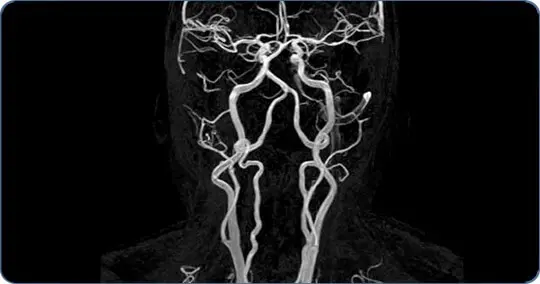

Игорю П. 72 года. У него при помощи УЗИ выявили критическое суждение мозговых сосудов до 95%. С точки зрения классического подхода к решению этой проблемы – нужна операция стентирования сосудов.

Мы использовали разработанные нами крайне эффективные методы оценки кровообращения головного мозга. Мы использовали разработанный нами атеросклеротический тест. Исследовали кровоток головного мозга, учли ключевые физические параметры движения крови по сосудам. И что важно, мы провели расчет степени компенсации кровотока мозга и определили, за счет каких сосудистых бассейнов (артериальных и венозных) можно данный резерв компенсации. Такие исследования дали возможность выстроить оптимальную лечебную тактику по оптимизации кровотока головного мозга. Сделал свой вклад и кардиолог клиники. Поскольку атеросклероз – это не только поражение мозга, но многих сосудов, включая сосуды сердца.

Комплексная адекватная диагностика как состояния самого мозга, так и сосудов была ключевым фактором при выборе тактики лечения и реабилитации.

Были диагностированы не только атеросклероз, но и критическое снижение скоростных показателей крови в сосудах мозга. Причем стали известны конкретные сосудистые бассейны, в которых кровоток был снижен критично. Более того, были выявлены причины атеросклероза. Не говоря уже о сопутствующей патологии, которые также могли привести к фатальному концу.